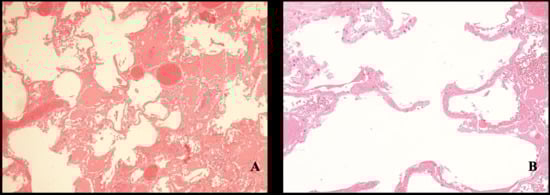

1. Introduction

2. Case Report